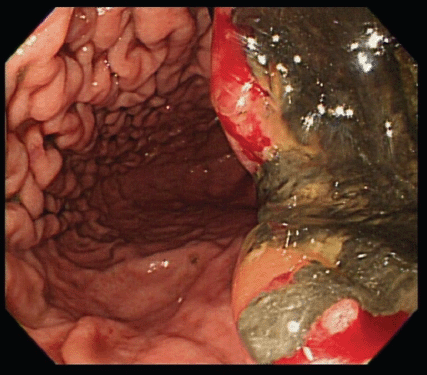

An upper gastrointestinal tract endoscopy led to the finding of a giant gastric ulcer over lesser curvature of the stomach (Figure 2). Pathology study of the biopsy specimen from the ulcer confirmed the nature of a poorly differentiated carcinoma (Figure 3) positive for cytokeratin AE1/AE3, with morphology patterns in favour of a gastric rather than a pancreatic origin. Immunohistochemical staining afterwards revealed only moderately positive expression of dihydropyrimidine dehydrogenase (DPD) (Rabbit monoclonal DPYD EPR8811: ab134922, Abcam, Cambridge, UK) (Figure 4) and totally negative expression of Bcl-2 (Clone bcl-2/100/D5, NovocastraTM HD, Leica Biosystems, UK) (Figure 5).

Figure 2. A giant gastric ulcer over lesser curvature of stomach (right half of the figure) revealed by upper gastrointestinal tract endoscopy.

Figure 3. Poorly differentiated carcinoma of stomach, lesser curvature site, endoscopic biopsy (haematoxylin and eosin stain ×400).